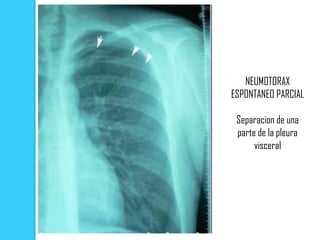

NEUMOTORAX

ESPONTANEO PARCIAL

Separacion de una

parte de la pleura

visceral

Signos radiológicos  Colapso pulmonar de mayor o menor un grado dependiente de la magnitud del neumotórax. Se considera total cuando hay un colapso pulmonar máximo. El grado de colapso es mínimo, cuando el espacio que hay entre la pleura visceral y parietal es menor de 1 cm.  La denominada " linea pleural " que es la pleura visceral del pulmón colapsado  3) Ausencia de trama vascular pulmonar distal. Suele ser de localización apical debido a la tendencia del aire a ascender.

NEUMOTORAX ESPONTANEO PARCIAL Separacionde una parte de la pleura visceral